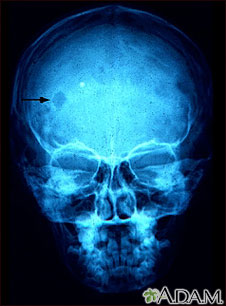

Eosinophilic granuloma - x-ray of the skull

This x-ray of the skull shows an eosinophilic granuloma (a lesion made-up of a type of white blood cell). This condition can range from a single eosinophilic granuloma to massive infiltration of skin, bone, and body organs.